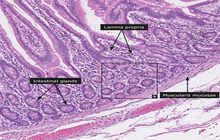

- General and specialized tissue and cell staining

- Prepare educational slides for students from all available tissues

Histological methods includes sample processing in the pathology laboratory, preparation of the slide and its examination under a microscope, sample fixation, molding, microtome cutting, staining and assembly of the slides.